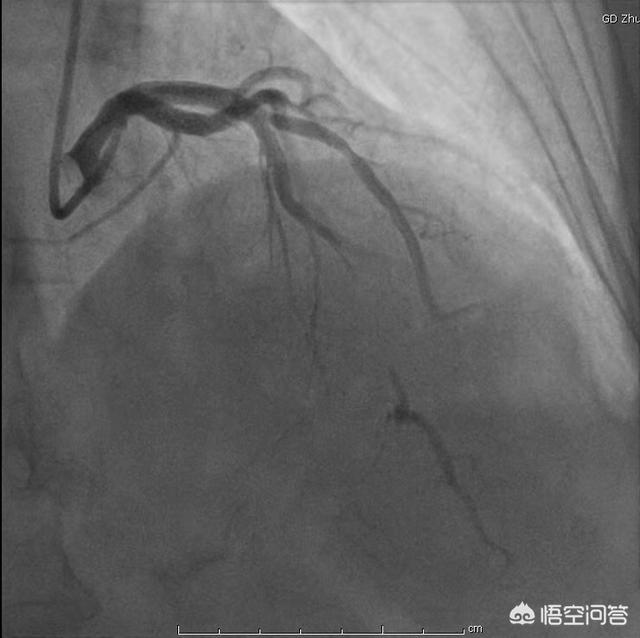

Enfin, il convient de rappeler qu'une simple copie des changements ST-T dans l'ECG ne suffit pas à déterminer s'il y a une maladie coronarienne. Si vous présentez un risque élevé de maladie coronarienne, vous pouvez utiliser l'électrocardiogramme dynamique et le test de plaque d'effort pour une évaluation préliminaire ; si vous êtes fortement suspecté de maladie coronarienne, vous pouvez utiliser l'angiographie coronarienne ou l'angiographie CTA pour établir un diagnostic final et définitif.